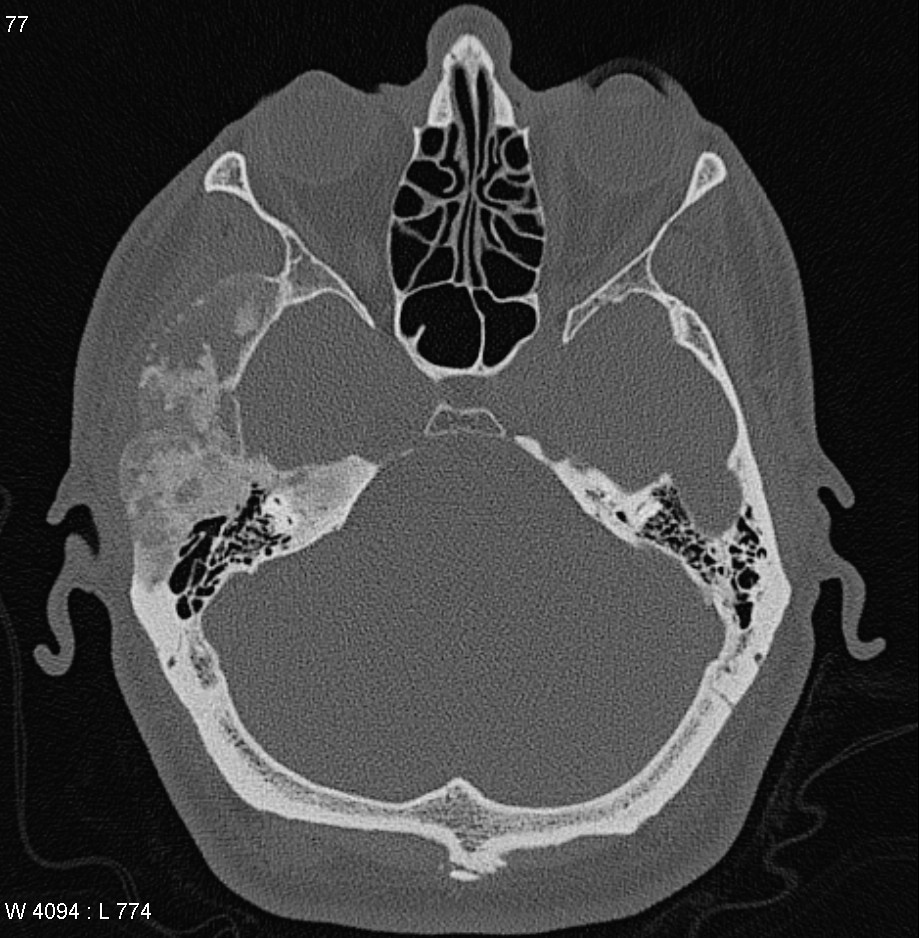

A) Schädel-CT eines 70-jährigen Patienten. B) Schädel-CT eines 30-jährigen Patienten. In einem Fall liegt eine Fibröse Dysplasie vor, in dem anderen ein Morbus Paget? Welches Bild zeigt am ehesten welche Erkrankung und warum?